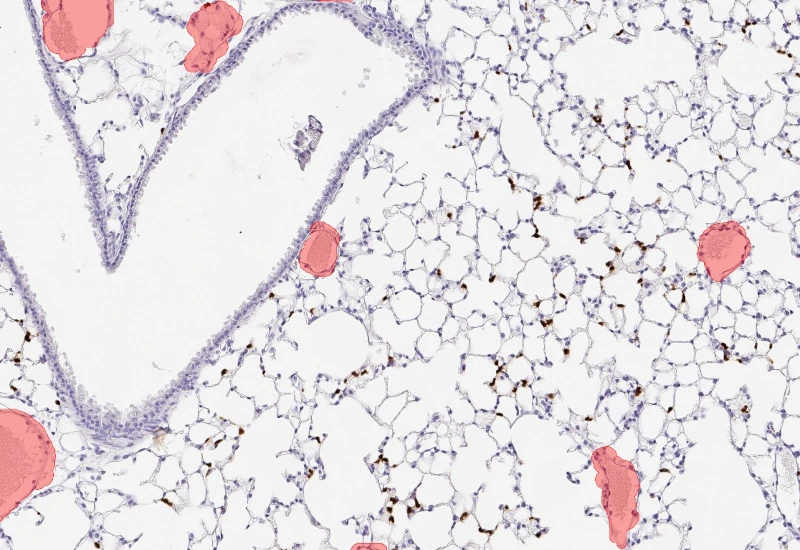

Segment nuclei and lung metastructures (total tissue, bronchioles, vessels, alveoli), detect cellular phenotypes within each component, and measure up to 20 morphometric parameters per metastructure and nucleus.

The Pulmo App segments nuclei as well as the metastructure components of lung, including total tissue, bronchioles, blood vessels and alveoles. Further it detects cellular phenotypes within the metastructure components. Each segmented metastructure/nuclei is measured for up to 20 morphometric parameters.